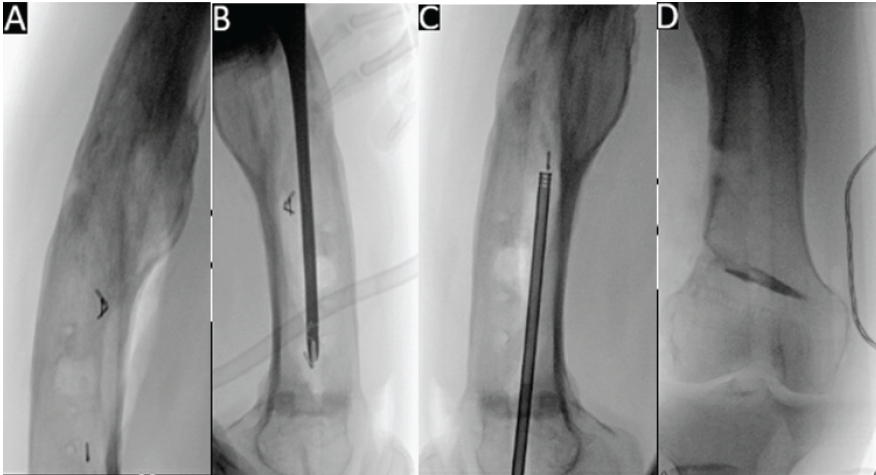

Initially, the bulk of the reamer head was removed by retracting the ball-tip guide wire; however, four small metal pieces remained in the canal (Fig. 2a). Next, a removal attempt using a series of differently sized graspers was made; however, this was only partially successful and very time-consuming (Fig. 2b). Then, the idea of extracting the debris using a laparoscopic suction instrument (Stryker® Inc) (Fig. 3) under fluoroscopy was conceived and successfully put into practice (Fig. 2c). Finally, once the canal was clear (Fig. 2d), a new RIA-2 set was used, and the procedure was completed successfully. The patient was given broad-spectrum antibiotics until speciation of cultures and was allowed to weight bear as tolerated on the right lower extremity.

Figure 2: Fluoroscopic images of four pieces of debris remaining in the canal after extraction of the reamer-irrigator-aspirator – two head (a), followed by attempted removal of debris using pituitary grasper (b), then successful use of laparoscopic suction device to remove retained debris (c), and a clear intramedullary canal (d).